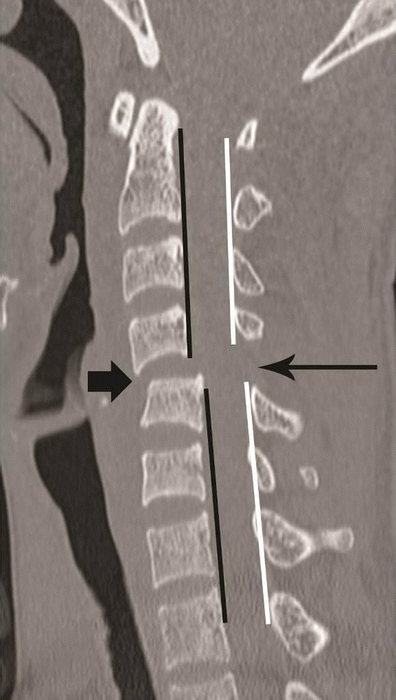

Flexion teardrop fracture. Sagittal CT image of cervical spine in a young patient following vehicular accident shows wedging of C5 vertebral body with an oblique coronal fracture of the anterior third of the vertebral body, dividing the C5 in to a smaller anterior triangular fragment (short arrow) and a large posterior segment. Retrolisthesis of the C5 vertebral body on C6 behind the fracture line and retropulsed C5 keeping alignment with the cranial C4 vertebral body—suggested by non-interrupted posterior vertebral line (black line), while triangular fragment keeping alignment with the caudal C6 vertebra—suggested by non-interrupted anterior spinal line (white line). Distraction of posterior column is suggested by widening of interspinous/interlaminar space at C4–C5 (long arrow). Facet joint subluxation was seen on the parasagittal images (not shown)